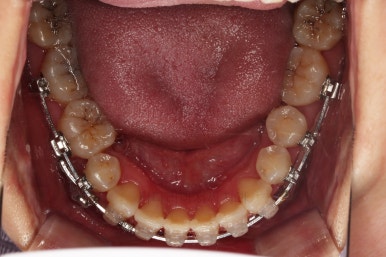

치열을 정리해 나갑니다.

치열이 매우 가지런해졌고, 아래 앞니 사이 틈새도 점점 오므려져 가고 있습니다.

발치 공간을 적극적으로 줄여 나갑니다.

이 과정에서 입매, 앞니 각도, 정중선 등을 신경 써줍니다.

아무래도 상하좌우 비어 있는 공간의 위치가 모두 달랐기 때문에 자칫하면 중앙선이 한 쪽으로 쏠려버릴 수 있기 때문이죠.

중앙선 개선을 위해 미니스크류와 다양한 장치를 활용해 주고요.

발치 공간도 많이 줄었네요.

중앙선, 교합 등을 더 신경쓰고 마무리를 합니다.

마무리 전에 부산교정치과 충치치료도 깔끔히 진행하게 됩니다.